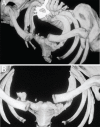

Unilateral and bilateral sternoclavicular joint (SCJ) dislocations are rare injuries. The difficulty in assessing this condition often leads to delay in diagnosis and treatment. We report a rare case of bilateral asymmetrical traumatic SCJ dislocations in a 45-year-old male. The right anterior SCJ dislocation was reduced in the emergency room (ER) and resulted in residual instability. The left posterior SCJ dislocation was asymptomatic and unnoticed for six months. It is important for ER physicians and orthopaedic surgeons to be able identify and treat this condition. All suspected SCJ dislocations should be evaluated by computed tomography (CT) scan for confirmation of the diagnosis and evaluation of both SCJs. Posterior SCJ dislocation is a potentially fatal injury and should not be overlooked due to the presence of other injuries. Surgical intervention is often necessary in acute and old cases.